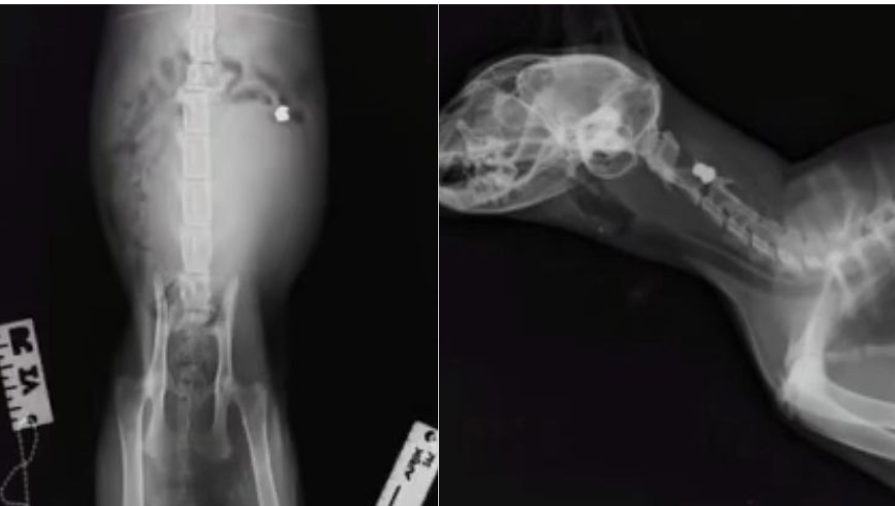

Local Isabel Carmona has shared X-ray images showing pellets lodged inside the animals’ bodies, claiming the injuries are the result of deliberate shootings carried out within the limits of Sabiote.

In a video circulating online, Carmona displays veterinary reports and radiographs that appear to show metallic pellets inside several cats.

One of the most serious cases involves a cat that may have suffered spinal damage. The animal is due to see a specialist to assess whether rehabilitation could allow it to regain basic bodily functions.